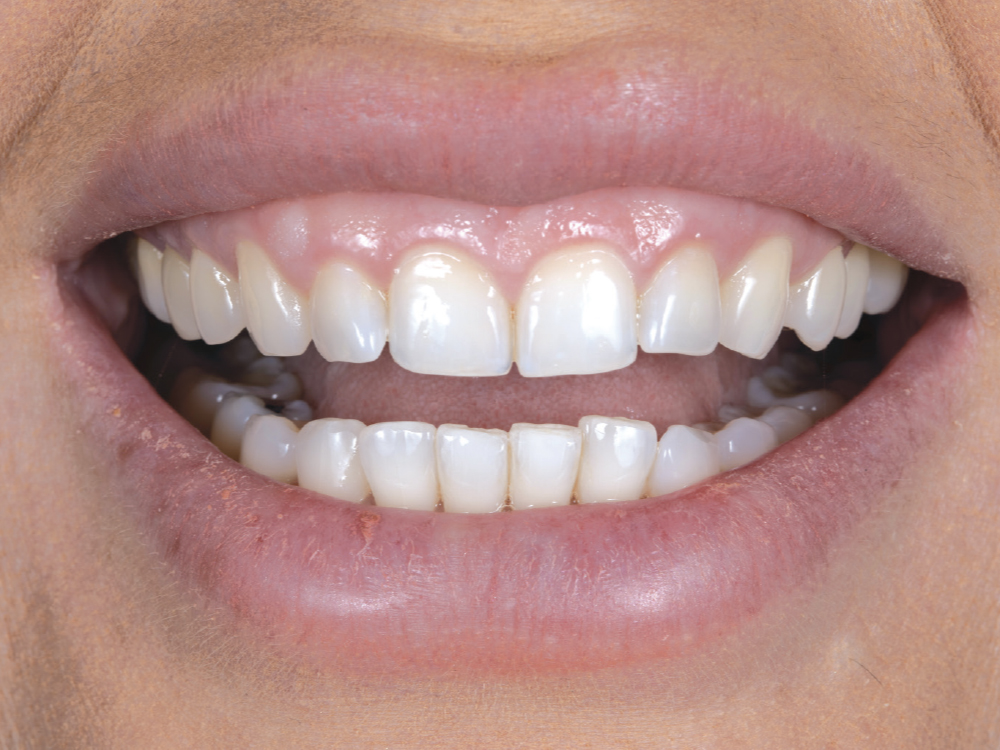

The Glidewell HT implant, custom hybrid abutment, and BruxZir Esthetic cement-retained restoration were successfully delivered without compromising the hard-or soft-tissue contours.

To protect against further damage to the teeth and the newly placed implant, an occlusal guard was prescribed.

Figures 22a–22c: The Glidewell HT implant, custom hybrid abutment, and BruxZir Esthetic cement-retained restoration were successfully delivered without compromising the hard- or soft-tissue contours. To protect against further damage to the teeth and the newly placed implant, an occlusal guard was prescribed.